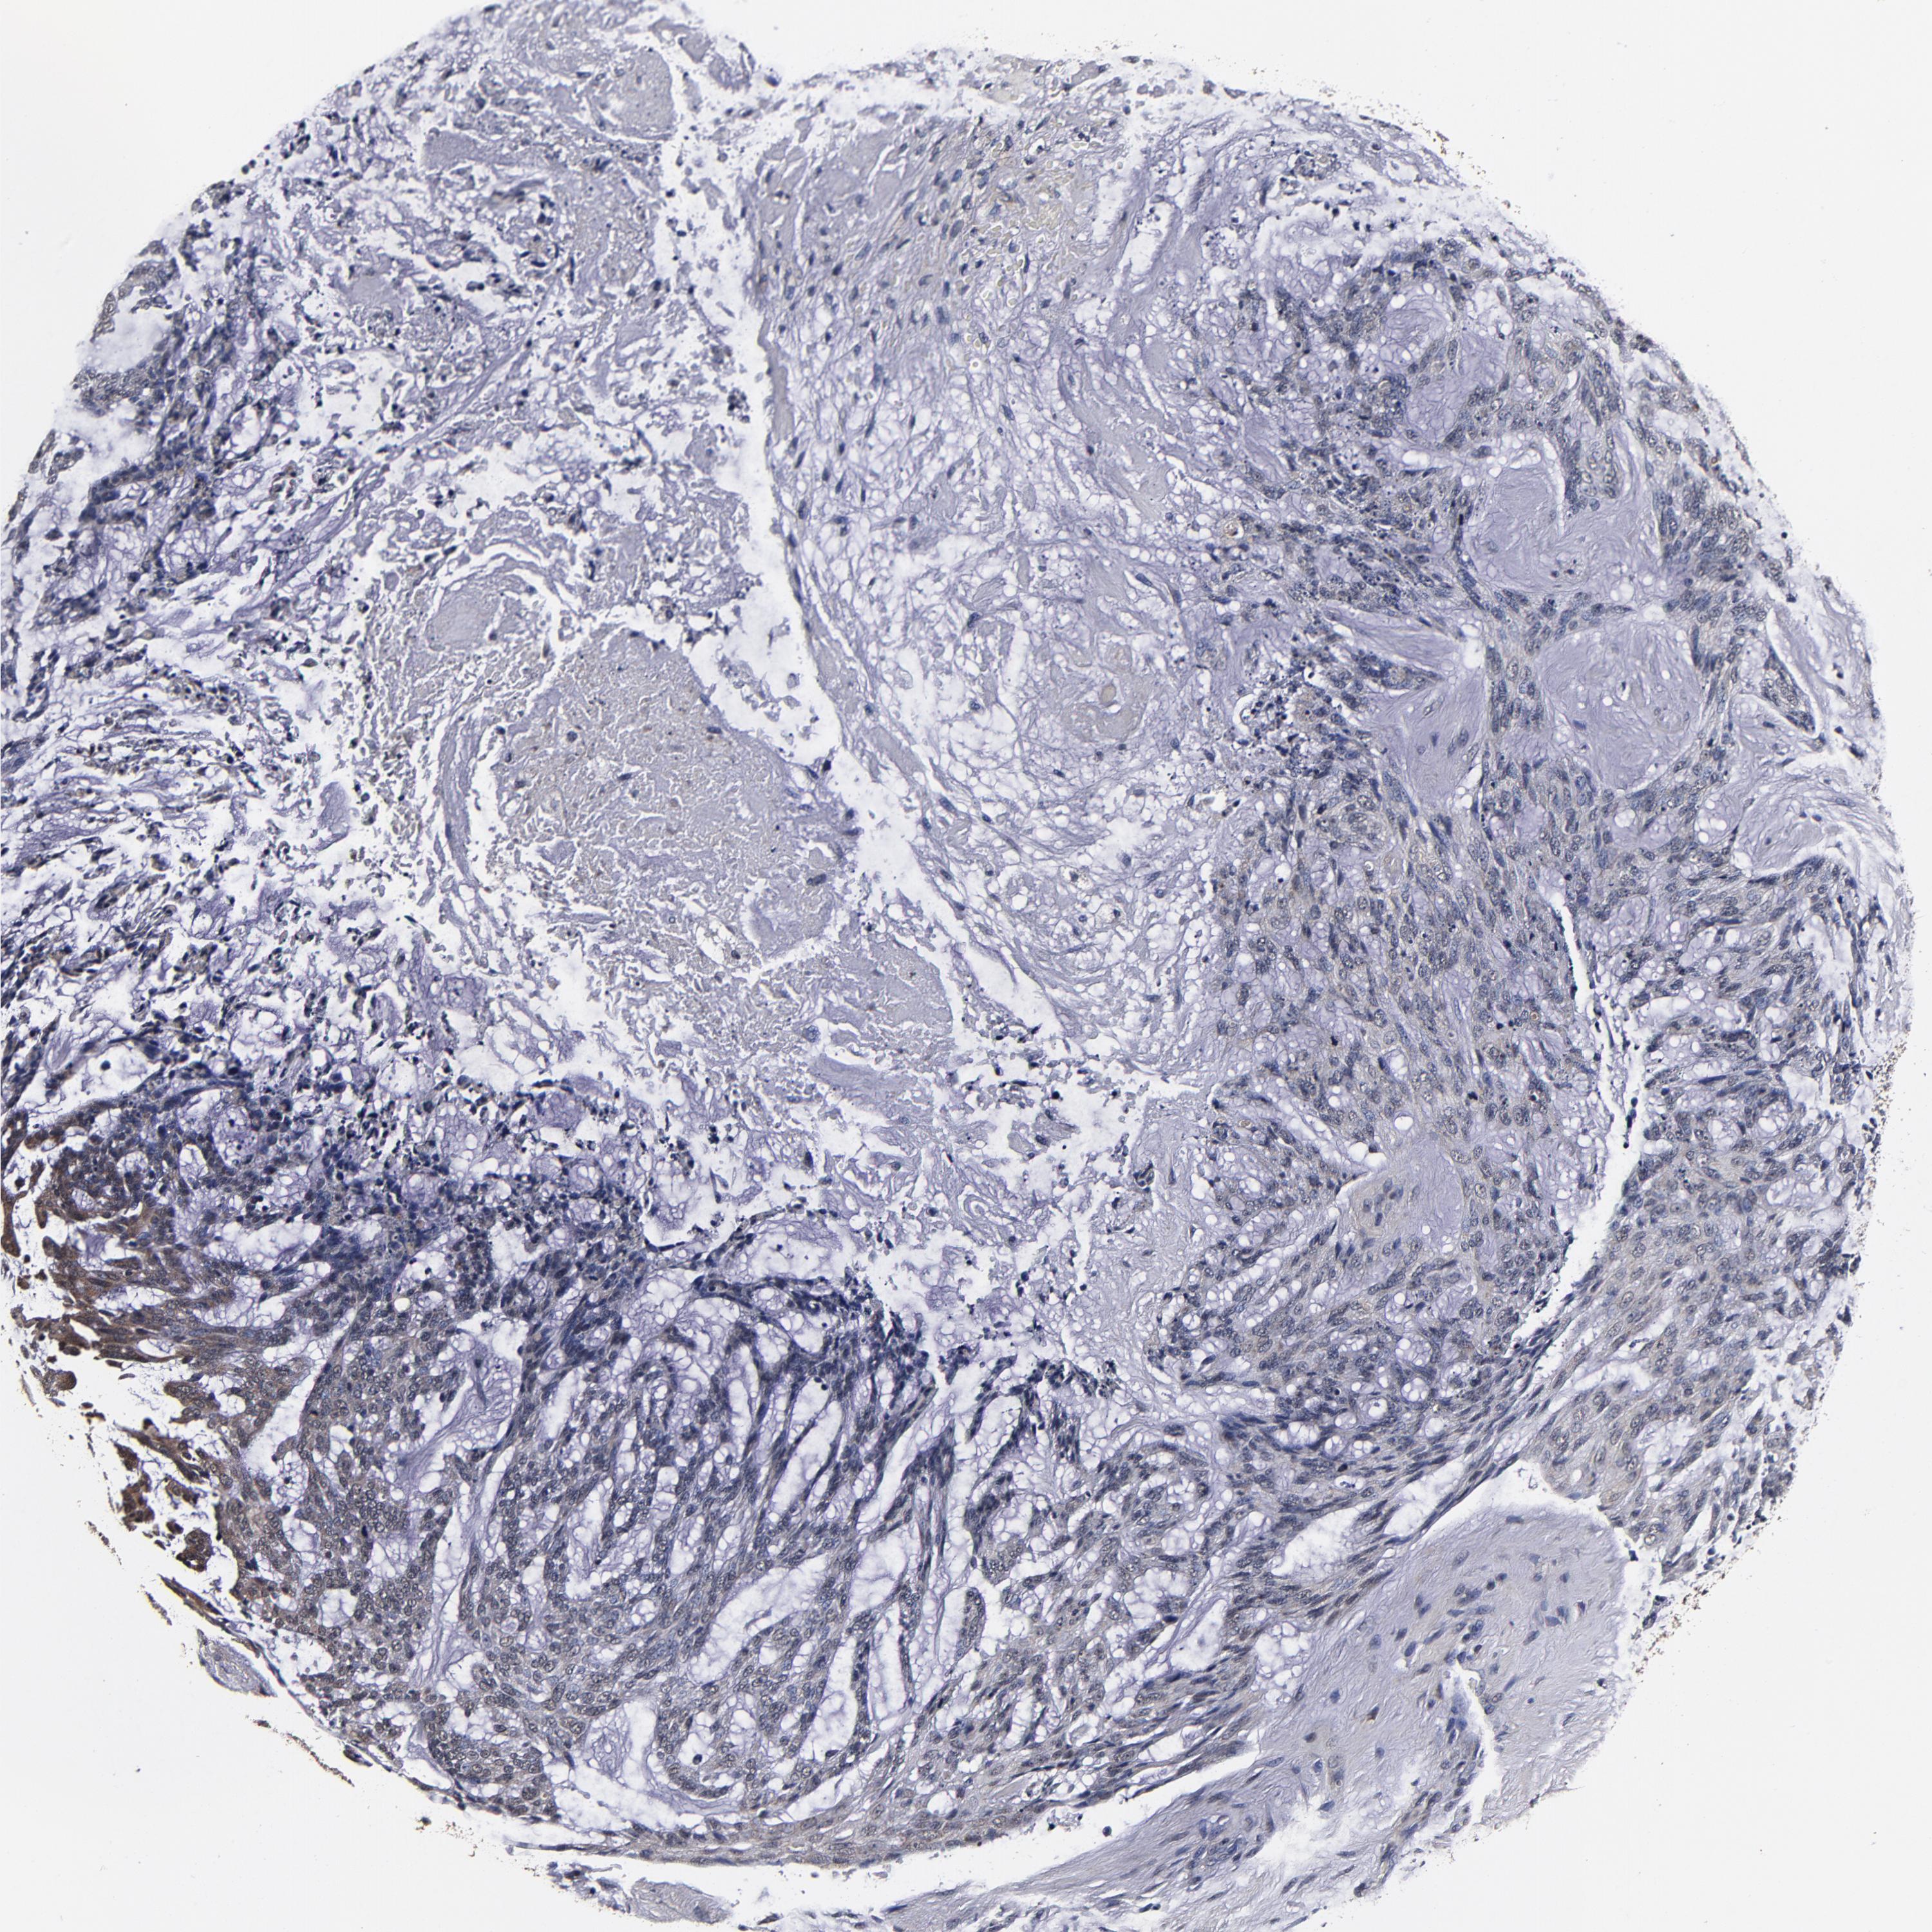

Basal cell and squamous cell cancer

SKIN CANCER - Protein expressioni

A mouse-over function shows sample information and annotation data. Click on an image to view it in a full screen mode. Samples can be filtered based on level of antibody staining by selecting one or several of the following categories: high, medium, low and not detected. The assay and annotation is described here.

Antibody stainingi

Antibody staining in the annotated cell types in the current human tissue is reported as not detected, low, medium, or high, based on conventional immunohistochemistry profiling in selected tissues. This score is based on the combination of the staining intensity and fraction of stained cells.

Each image is clickable and will lead to virtual microscopy that enables deeper exploration of all samples and also displays staining intensity scores, fraction scores and subcellular localization as well as patient and tissue information for each sample.

Antibody HPA040390

Basal cell carcinoma